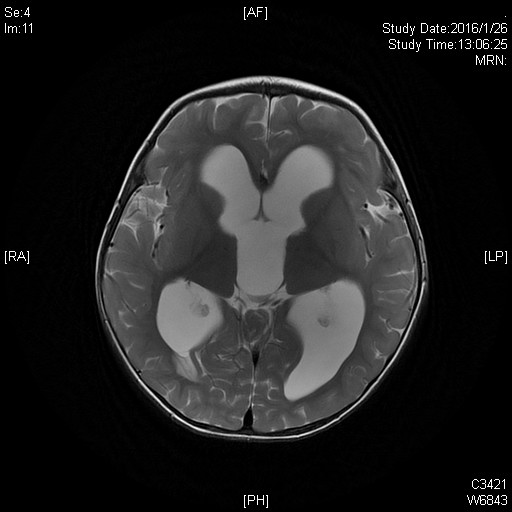

患者小萌(化名)是一名来自河南的17个月大小男孩。小萌的父母在来我院5天前发现他眼姿不正,在当地医院检查,发现了四脑室占位、脑积水。因病情的的复杂性,当地医院不能处理,建议来我院神经外科王贵怀主任门诊就诊。

髓母细胞瘤是颅内恶性程度最高的胶质瘤,生长迅速,手术不易全部切除。经过神经外科科内讨论,为小萌制定了详细的手术方案,行肿瘤切除术。麻醉科也给予小萌特别的关爱,在手术室,麻醉科张欢主任和主治医师魏昌伟上下同时开工,一位动脉穿刺,一位股静脉植管。麻醉过程紧张有序,有条不紊。主刀医生王贵怀主任擅长高位颈髓和脑干肿瘤手术,处理四脑室肿瘤游刃有余。手术中肿瘤暴露、分离、切除、止血,步步为营,干净利落。手术很成功,肿瘤全切,约5.0mm×3.5mm,足有鸡蛋大小。术后小萌入ICU,在ICU的精心治疗下,他恢复很快,术后第2天返回普通病房治疗。术后住院日,小萌病情平稳,恢复良好,于2016年2月19日出院。术后病理证实小萌脑部肿瘤为髓母细胞瘤。